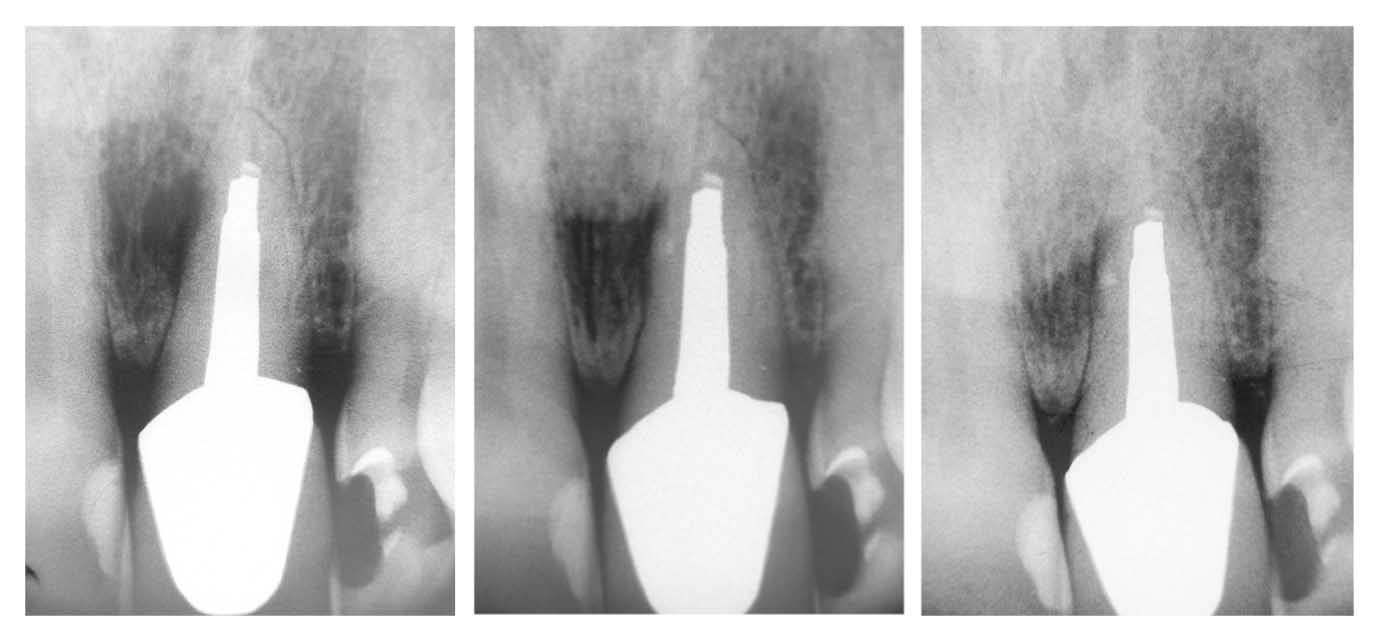

Seitenkanal 21 42 Monate Röntgenbilder

Veröffentlicht 7. Juni 2009 am 1376 × 640 in Saving hopeless teeth (V) – Frontzahn mit Seitenkanal – Verlaufkontrolle nach 3,5 Jahren